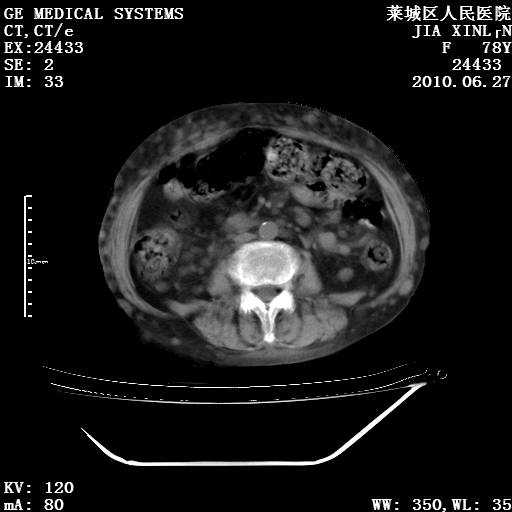

以下是引用胡宇在2010-7-2 19:11:00的发言:[br]神经纤维瘤的特点为:肿块呈多发性、数目不定,少的几个,多的可成百上千难以计数。小的如米粒,大的似拳头,甚至可达十数公斤以上。可松弛地悬挂于皮表,皱褶及松弛可致畸形明显。神经纤维瘤沿神经干的走向生长时呈念珠状,或蚯蚓块状形结节。此外神经纤维瘤皮肤可出现咖啡斑,大小不一,形如雀斑小点状,或大片状,分布与神经纤维瘤肿块的分布无关。肿瘤数目不多的患者,皮肤色素咖啡斑状沉着是纤维神经瘤的重要诊断之一。 本病多发于躯干,有时出现于四肢及面部,患者常合并许多疾病应予重视加以区别。 [br] [br] [br] [br]lyb999说 [br]